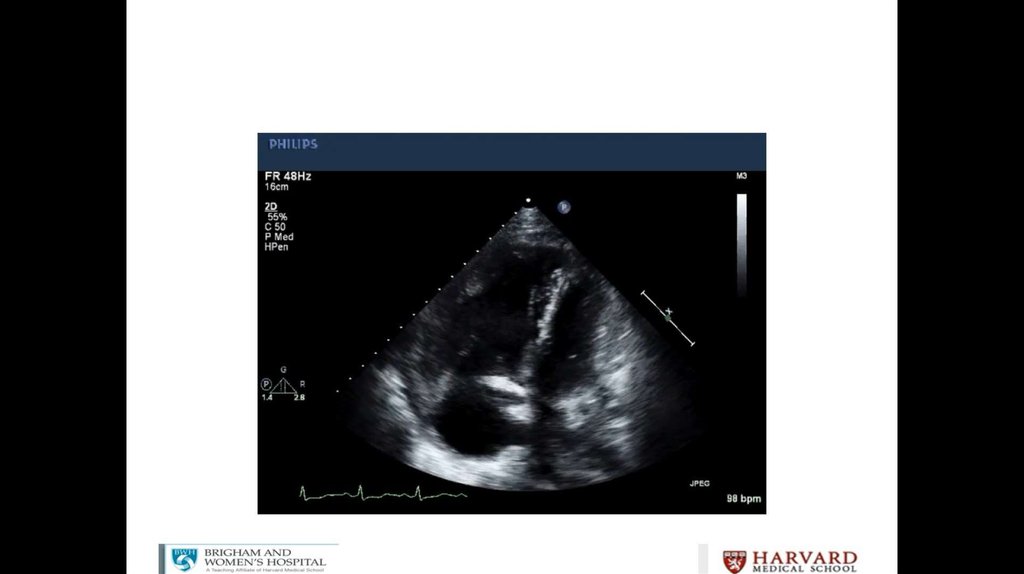

Litrasound in the ICU: What Every Intensivist Should Know